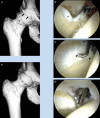

Results: Several studies reported reasonably successful outcomes in the arthroscopic management of FAI in athletes, and 1 study reported on open surgical correction of this disorder. Few major complications have been described.

Conclusions: When the diagnosis is given early, some athletes may benefit from a rehabilitation strategy that includes training modifications to protect the at-risk hip. When indicated, arthroscopic surgery can address the joint damage and correct the underlying impingement. Although the joint may not be normal, successful results with return to sports can often be expected.